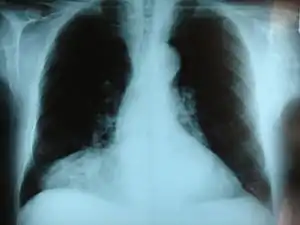

![]() | |

| پرتونگاری ریه نشان دهنده فتق «مورگانی» | |